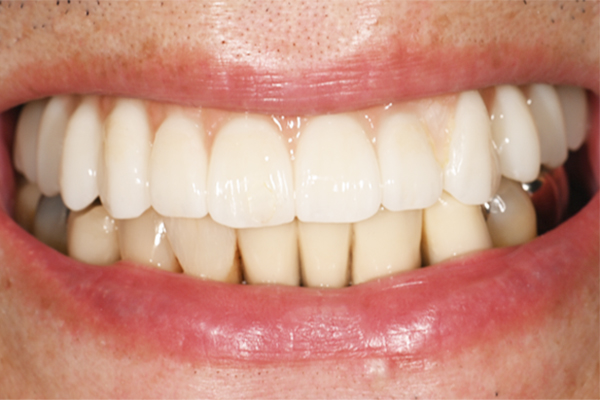

| 主訴 | 奥歯で噛めない、顎が痛い |

|---|---|

| 治療内容 | 奥歯のインプラント治療、前歯・奥歯の被せ物治療 |

| 治療期間 | 6ヶ月 |

| 治療費 | 350万円 |

| 治療リスク | 被せ物をつけた初期の段階で歯がしみることがある(時間とともに改善する) インプラント治療後に3日程度痛みと腫れを伴うことがある |